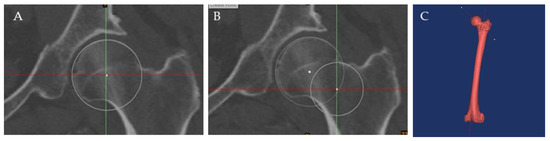

| Lesser trochanter version | 38.54° ± 7.86° | 16.99° to 54.38° | 0.98 | 0.98 |

| Femoral anteversion | 11.84° ± 10.06° | −17.63° to 43.98° | 0.99 | 0.99 |